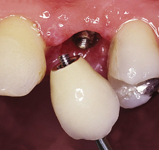

Náhrada jednoho zubu pomocí implantátu je možná také v postranním úseku chrupu. Při ztrátě většího počtu zubů ve frontálním nebo postranním úseku může být mezer uzavřena větším počtem jednotlivých implantátů.

Při ošetření pomocí jednotlivých implantátů zůstávají sousední zuby neporušené – intaktní. Při klasickém ošetření pomocí můstků musejí být tyto zuby obroušeny!